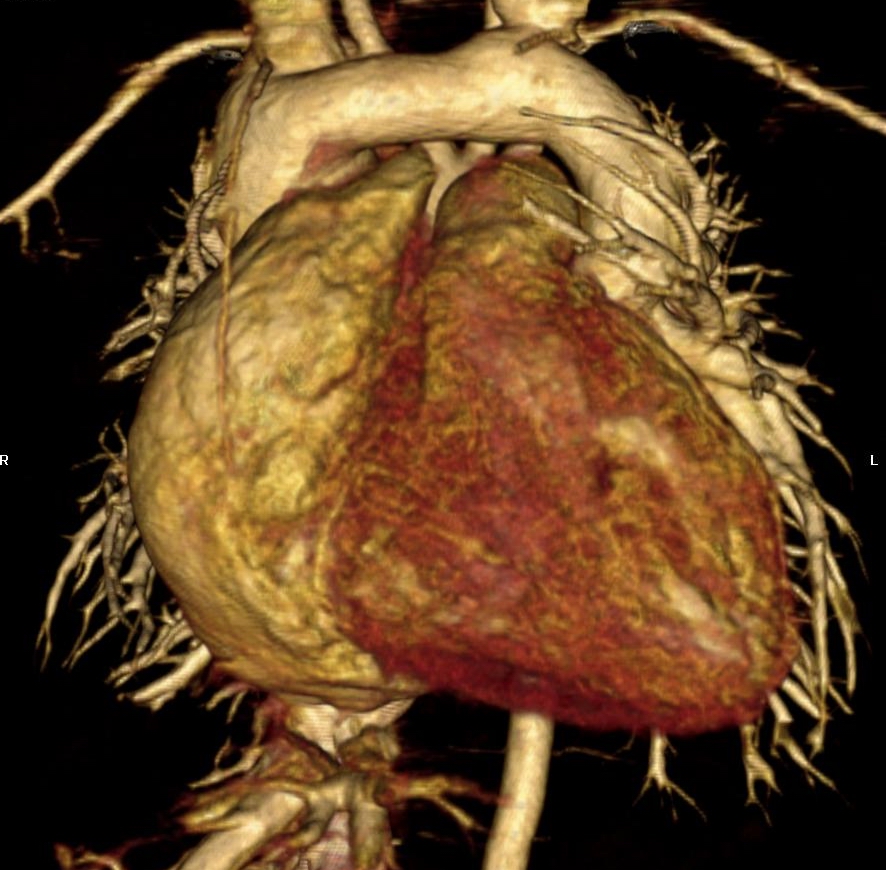

cardiomegaly on x-ray 11/F

Kyungsun Nam, Department of Radiology, Yonsei University College of Medicine

HIT : 16